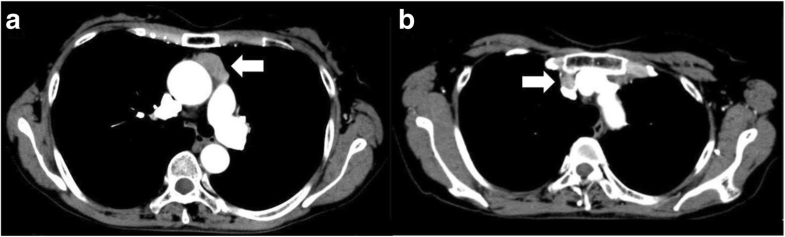

Chest CT image. A tumor (30 × 30 × 14 mm) without invasion localized in the anterior mediastinum (a). Enlargement of lymph node (b)

A 61-year-old woman was admitted to be evaluated for hypoglycemia and hypokalemia. Laboratory data revealed elevation of serum cortisol and ACTH levels. Overnight administration of 8 mg dexamethasone did not suppress plasma ACTH. Chest CT demonstrated a tumor of 30 mm in diameter and enlargement of the lymph node at the anterior mediastinum. Ectopic ACTH syndrome was suspected and total thymectomy and lymph node dissection were performed. The histopathological examination indicated typical carcinoid tumor and mediastinal lymph node metastasis, and immunohistochemical staining was positive for ACTH. The plasma ACTH level decreased immediately after surgery. She received postoperative radiation therapy of 60 Gy.